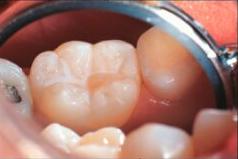

Az őrlőfogak rágófelszínén található barázdák egyedileg változó mélységűek, a mély barázdák alján gyakran mikroszkopikus repedések találhatóak, amelyek keskenyebbek, mint a fogkefe sörtéi ezért nem tarthatók tisztán. A barázdazárt felületek ezzel szemben simák és ezáltal könnyen tisztán tarthatók.

Első lépésben a fogak megtisztításra kerülnek, majd leszárítjuk őket és ezt követően egy enyhe savval felületét felérdesítjük. Ezt követi a barázdazáró anyag ecsettel történő felhelyezése. Az anyag maga úgy képzelhető el, mint egy folyékony tömőanyag, amely egyenletesen elterülve feltölti a barázdát. Következő lépésként a felhelyezett barázdazáró anyagot speciális, kék fényű lámpával keményítjük meg. Utolsó lépésként ellenőrzésre kerül, hogy a barázdazárás a fogsor záródását nem akadályozza-e. Amennyiben felmerül ennek gyanúja, úgy a megfelelő helyen csiszolással elvékonyítjuk a felvitt anyagot, majd polírozzuk.